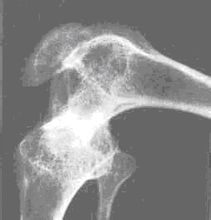

維生素D缺乏會導致少兒佝僂病和成年人的軟骨病。佝僂病多發於嬰幼兒,主要表現為神經精神症狀和骨骼的變化。神經精神症狀上表現為多汗、夜驚、易激惹。骨骼的變化隨年齡、生長速率及維生素D缺乏的程度等因素有關。可出現盧骨軟化、肋骨串珠等。骨軟化症多發生於成人,多見於妊娠多產的婦女及體弱多病的老人。最常見的症狀是骨痛、肌無力和骨壓痛。

維生素D主要用於組成和維持骨骼的強壯。它被用來防治兒童的佝僂病和成人的軟骨症,關節痛等等。患有骨質疏鬆症的人通過添加合適的維生素D和鎂可以有效的提高鈣離子的吸收度。除此以外,維生素D還被用於降低結腸癌、乳腺癌和前列腺癌的機率,對免疫系統也有增強作用。維生素D的作用機制。維生素D的前體(生成維生素D的原料)存在於皮膚中,當陽光直射時會發生反應轉化為維生素D3,D3分子被運送到肝臟並且轉化為維生素D的另一種形式25位單脫氧膽固醇,這種形式的效用更大。然後25位單脫氧膽固醇又被轉運到腎形礦脈並在那裡被轉化為1,25位二羥膽鈣化(甾)醇,這種形式是維生素D最有效的狀態。然後維生素D將和甲狀旁腺激素以及降血鈣素協同作用來平衡血液中鈣離子和磷的含量,特別是增強人體對鈣離子的吸收能力。維生素D不應該用於血鈣過高的病人,或者血液中鈣離子含量偏高的人。另外對患有腎結石和動脈硬化的病人來說也必須小心使用,因為維生素D可能會引起他們的甲狀旁腺疾病,削弱腎功能甚至引起心臟疾病。

佝僂病和骨質疏鬆:維生素D可堅固骨骼,預防兒童佝僂病和老年骨質疏鬆症。